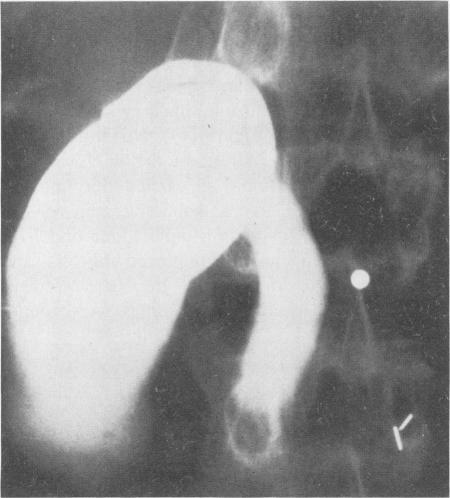

Intramural hematoma of the duodenum: a diagnostic roentgen sign.

Radiology. 1954 Dec;63(6):823-31. doi: 10.1148/63.6.823.